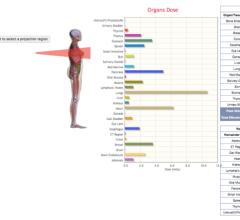

Virtual Phantoms Inc. announced the release of VirtualDoseIR, a tool for assessing organ dose from interventional radiology (IR) procedures. Like its VirtualDose CT product for computed tomography, VirtualDoseIR combines a family of anatomically realistic human phantoms, advanced Monte Carlo simulations, and an easy-to-use web interface to provide realistic calculations of dose to a diverse patient population.